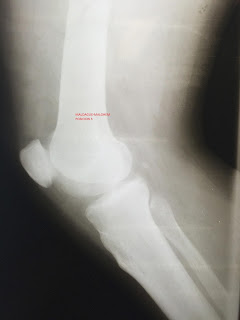

Rodilla flotante con lesion vascular

Inicia padecimiento actual el dia 27 /03/16 aproximadamente a a las 11 hrs al encontrarse manejando motocicleta de 150 cc sin protección pierde el control de esta y es proyectado 5 metros aproximadamente con contusión directa en miembro pélvico izquierdo a nivel del muslo con objeto desconocido  produciéndole una lesión por atrición con exposición muscular y abundante sangrado Es atendido por personal pre hospitalario 50 min después  con técnica de empaquetado  e inmovilizado  para su traslado a unidad hospitalaria. Llega a nuestra unidad al servicio de urgencias para su valoración  a las 14hrs.

Paciente activo reactivo obedese ordenes verbales presenta movilidad voluntaria y leguaje coherente con mucosas deshidratadas con tegumentos palidos  cabeza normocefala sin endostosis ni exostosis con presencia de contusiones faciales  con pupilas  isocoricas normo reflecticas cuello cilindrico simétrico con tráquea centra en este momento inmovilizado con collarin rígido  torax normolineo con campos pulmonares bien ventilados con adecuada amplexacion y amplexion  ruidos cardiacos de adecuada intensidad y frecuencia aumentada sin agregados patologicos  abdomen blando depresible sin datos de irritación peritoneal.

Extremidades torácicas integras simétricas eutróficas fuerza 5/5 con dermoabrasiones en ambas extremidades.

Extremidades inferiores asimétricas a expensas de izquierda la cual se encuentra con herida de aproximadamente 30cm con bordes mal definidos por herida por atriccion con sangrado activo en cara anteromedial de muslo izquierdo la cual abarca piel, tejido  subcutáneo y musculo con necrosis donde a la palpación se encuentra comunicación con foco de fractura,  distalmente en región anterior de la pierna izquierda se observa herida de 3cm aproximadamente con bordes mal definidos con  exposición ósea  y con sangrado activo con presencia de micelas , pulsos distales  no presentes (tibial posterior , pedio y popitleo) proximales  no presentes (femoral)  y llenado capilar ausente   con  cambios de coloración con palidez generalizada con disminución de la temperatura  fuerza no valorable extremidad contralateral sin alteraciones aparentes.

Se solicita valoración por cirugia general por la aparente lesión vascular Diagnosticando una lesión completa de arteria femoral Por lo que ingresa a quirófano de urgencias para reparación vascular Se entra de a quirófano de manera conjunta para lavado y desbridamiento de fractura expuesta  y fijación externa como protocolo de control de daños.

Dxs:

Politraumatizado  Choque hipovolémico grado  III Rodilla flotante  FRASER  I Fractura expuesta gustillo III C  diafisiaria  de fémur izquierdo 32 A 3 .1   IO 5  MT 4  NV 3 por AO

Fractura expuesta gustillo II diafisiaria de tibia y peroné izquierdo   42  B1.3    IO 2   MT2   NV 1 por AO.